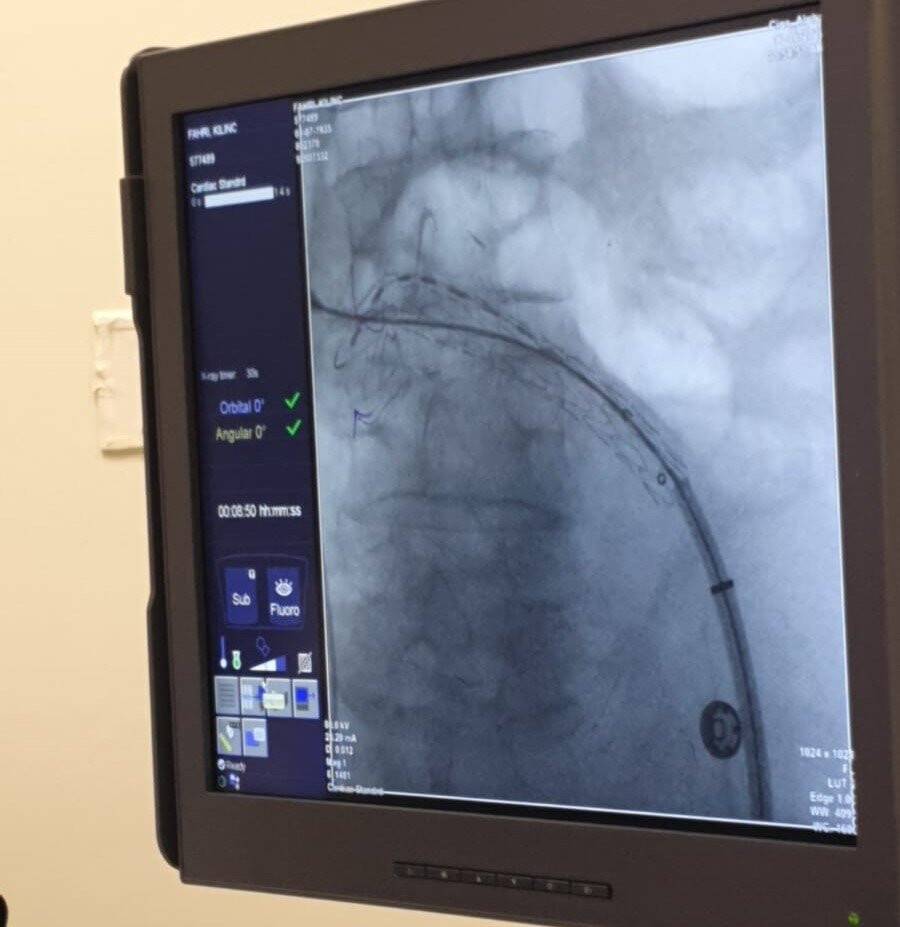

Kalp ve Damar Cerrahi Uzmanı Dr. Mehmet Kirişçi liderliğinde hastaya riskli olan açık ameliyat yerine kapalı ameliyatla tedaviye başlandı.

Hasta Fahri Kılınç için özel olarak getirilen stent-greft üstü özel bir kumaş kaplı olan tel kafes, hastalıklı damar bölgesine yerleştirildi. Yapılan kapalı operasyon sonrası hastanın damarı normal çapa indirilerek sağlığına kavuştu.

Kılınç'ın karnındaki damarın karpuz büyüklüğünde olduğunu söyleyen Dr. Kirişçi, "Normal şartlarda bu çap oluşana kadar ölümle sonuçlanabilirdi. Nihayetinde biz, hastamızın kasığından girerek anjyo-greft ile özel olarak getirttiğimiz stent-greft ile kapattık ve orada balonlaşan damarı tamamen kapattık. İşlem sonrası hastamızın var olan şikayetleri geriledi. Balonlaşan damarın kanlanması da kapandı ve oradaki anevrizmatik yapıyı ortadan kaldırmış olduk. Hastamız gayet konforlu ve taburcu noktasına geldi. Yani damarı balon gibi düşünelim ve büyüdükçe patlama riski artar. Yani damar standardın üzerinden yaklaşık 10 santimetre büyümüş. Eğer buraya gelmeseydi ölümle sonuçlanabilirdi" dedi.